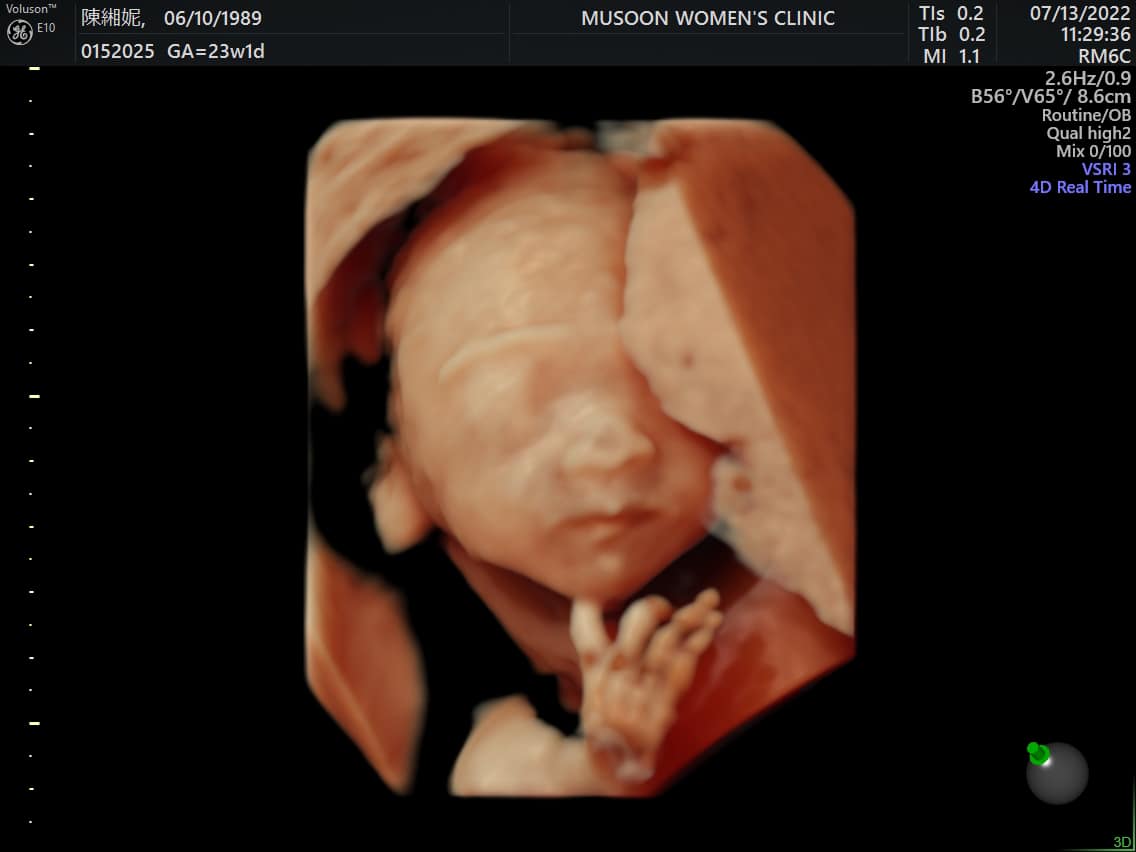

歌手謝和弦與老婆莉婭(陳緗妮)去年4月登記結婚,沒想到在滿週年前夕,竟爆出男方與祈錦鈅的烏龍緋聞,夫妻倆一度吵到鬧離婚,掀起不小的騷動!殊不知幾天後便驚喜宣布懷孕喜訊,感情瞬間重修舊好,彷彿什麼事情都沒發生過,讓外界看得一頭霧水。如今,莉婭已經懷有身孕五個月,並大方公布寶寶性別,掀起網友的高度關注與討論!

謝和弦13日在臉書曬出寶寶的超音波照片,並驚喜公布孩子的性別,「我要變女兒奴了,哈們!」,更笑稱前世的情人這輩子是來管教自己!只見照片中,女兒的五官已經相當清楚,還能看見可愛的小手扶著下巴,好像是刻意擺好姿勢給爸爸、媽媽看,模樣相當可愛!而莉婭也現身留言區笑回,「謝音悅跟謝燙燙一起管爸爸」,互動超級閃!